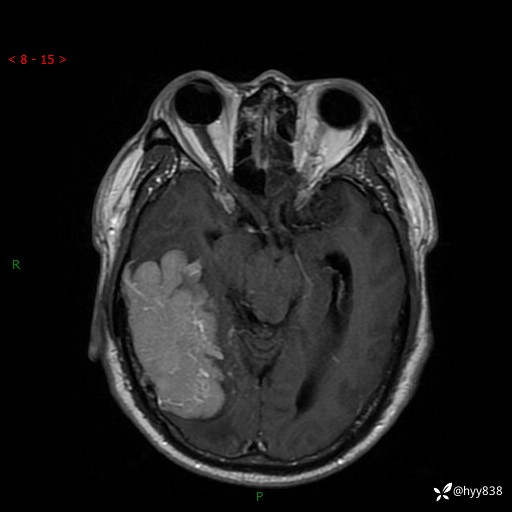

患者性别:男

患者年龄:56岁

简要病史:外院CT提示脑膜瘤,为进一步诊治来我院

临床诊断:颅脑占位

治疗经过:手术

讨论:病变性质?

颅脑MRI平扫+增强

脑膜瘤 (78)

脑膜孤立性纤维性肿瘤/血管外皮瘤 (1)

单发性纤维性肿瘤 (39)